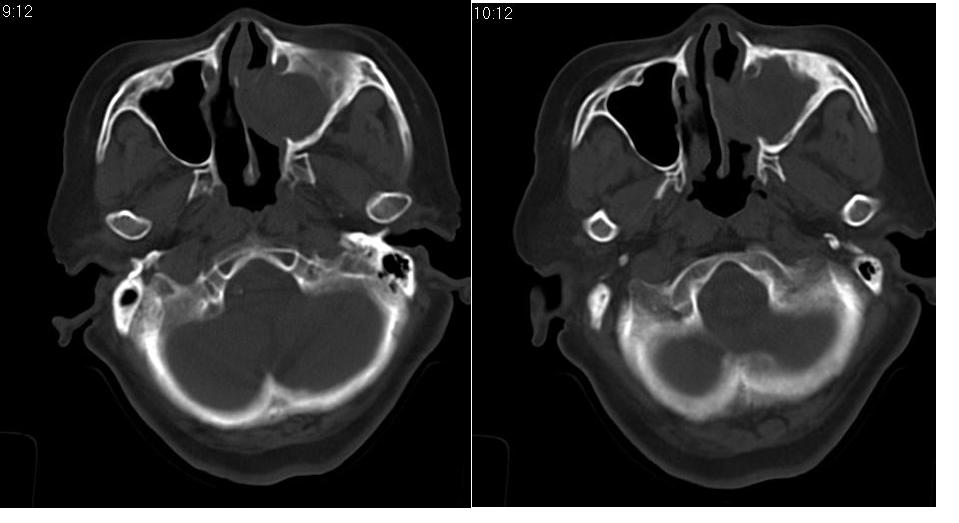

女 70岁,左侧上颌窦腔内肿物。

左侧颌窦内可见高密度影充填,窦壁增厚 考虑 左颌窦囊肿 慢性炎症

左侧上颌窦内软组织影,略呈膨胀性,窦壁骨质增生硬化,考虑为黏膜下囊肿.左侧筛窦炎

左侧上颌窦内软组织密度影,窦壁骨质增厚,密度增高,窦口扩大,考虑左侧上颌窦慢性炎症,息肉样变。

左侧上颌窦窦内可见高密度影充填,窦壁增厚,考虑左上颌窦窦囊肿,慢性炎症.